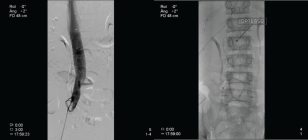

Acute osteomyelitis (AOM) is defined as an inflammation of the bone secondary to infection. Among the most common complications of AOM is the development of a periosteal abscess and the extension of the focus locally to muscle (pyomyositis) and/or joint (osteoarthritis). However, complications with much lower incidence have been described, including deep vein thrombosis (DVT) and septic pulmonary embolisms (SPE), mainly associated with S. aureus infections. The AOM + DVT + ESP triad is a fairly uncommon entity in the pediatric population; however, if it is not diagnosed and treated in time, it implies a high morbidity and mortality. Treatment, which must be early and aggressive, includes targeted antibiotic therapy, anticoagulation, and focused control surgery. In this article, we describe the case of a 14-year-old boy with disseminated staphylococcal infection associated with the triad AOM+ DVT + SPE.